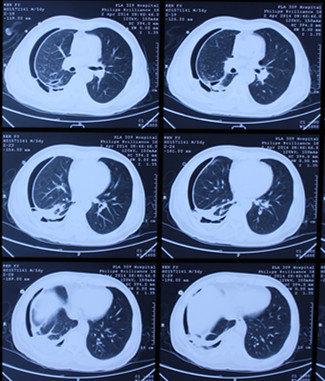

我是一名患有空洞型肺结核的患者,这是一个让人倍感焦虑和挣扎的疾病。空洞型肺结核是一种严重的肺结核病变,治疗过程漫长而痛苦,闭合时间也因人而异。

时间慢慢流逝,我努力配合治疗,坚持不懈。终于,在经过一段时间的治疗后,医生告诉我,我的肺部的空洞已经开始闭合了。那一刻,我欣慰而感动,这是我坚持治疗的动力和信心所在。